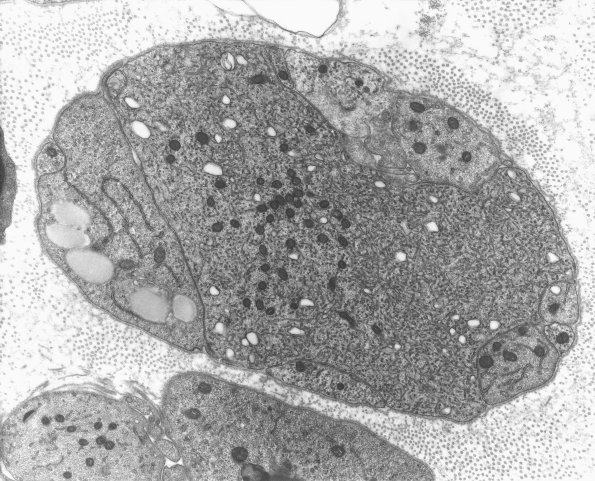

Very large growth cones filled with densely compacted material were seen in obstructed regenerating axons. (electron micrographs)